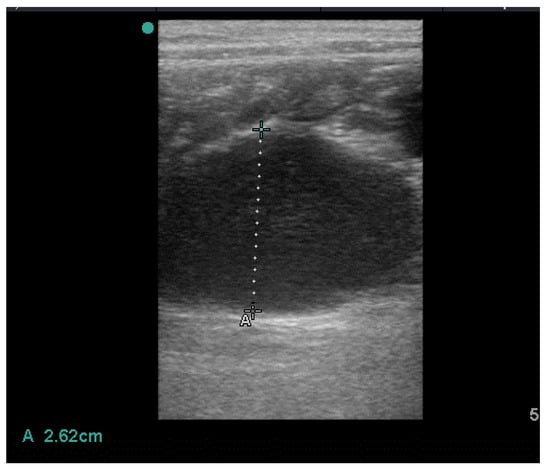

2. History and Clinical Findings

3. Treatment and Follow up